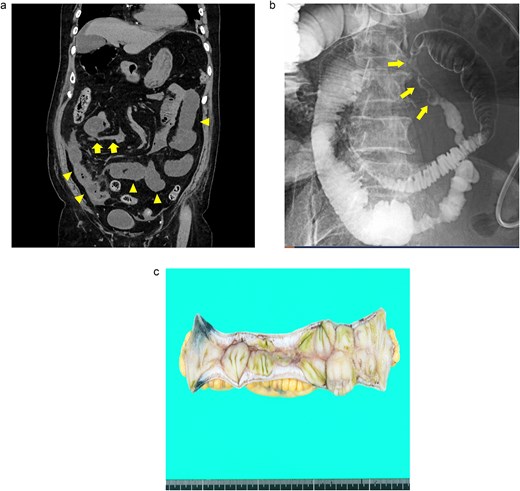

An 82-year-old man presented with recurrent nausea and abdominal pain that had persisted for 3 days. His vital signs were stable, and laboratory test results were as follows: a normal WBC count (3500/μl), elevated CRP concentration (35.4 mg/dl), slight anemia (Hb level:11.7 g/dl), normal Lac concentration (0.8 mmol/L), elevated BGL (259 mg/dl), and elevated HbA1c level (7.3%). Plane CT revealed a segmental stricture without wall thickening in the distal ileum. His proximal small bowel was dilated, and increased attenuation was observed within the adjacent mesenteric fat (Fig. 3a). No HPVG or mesenteric emphysema was observed. The preliminary diagnosis was enteritis without bowel ischemia. The patient was initially tolerant of the conservative treatment and discharged. However, abdominal pain recurred 5 days after discharge, necessitating readmission. Because his symptoms of nausea/vomiting and abdominal pain gradually worsened, a long intestinal tube was placed for luminal decompression. Fluoroscopy revealed segmental, irregular, patchy luminal narrowing of the distal ileum (Fig. 3b). Exploratory laparoscopy revealed a 12-cm-long segmental bowel stricture 30 cm from the ileocecal valve, which was resected. Pathological examination revealed multiple patchy, longitudinal ulcers, and wall thickening at the stenotic site, with granulocyte infiltration and fibrosis extending from the muscularis mucosae through the proper muscle layer. No signs of tumors or IBD were noted (Fig. 3c). The postoperative course was complicated by aspiration pneumonia and transient abdominal pain without intra-abdominal sepsis. He gradually recovered and was transferred to a satellite hospital for continuing care on the 50th postoperative day. The patient’s clinical course at the satellite hospital was uneventful. By 7 months after surgery, he had not had any recurrences of the abdominal symptoms.

Case 3: (a) Plain CT of the abdomen. The arrows indicate a segmental stricture in the distal ileum. The arrowheads indicate dilatation of the small bowel. (b) Fluoroscopy with a long intestinal tube. The arrows indicate segmental, irregular, patchy luminal narrowing of the distal ileum. (c) Macroscopic view of the resected specimen. Multiple longitudinal ulcers with irregular wall thickening are visible in the affected areas.